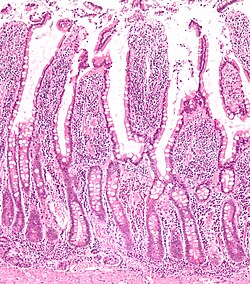

Normal small bowel

- AKA normal small intestine.

Histology

The Gastrointestinal pathology article covers basic histology of the GI tract.